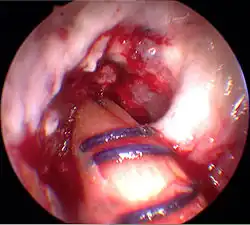

Le premier temps de l'opération est le prélèvement du transplant. Une incision d'environ 4 cm dans la peau sur la partie interne de la tête du tibia, au-dessus de la «patte d'oie» permet le prélèvement successif sur les tendons semi-tendineux et gracile. Les prélèvement sont faits sur les deux tendons avec un « couteau à tendon », et ont une longueur d'environ 28 cm. Ils sont pré-tendus avec un dispositif spécial, et cousus ensemble en un cordon multiple, par exemple quadruple. La longueur du transplant est alors de 7 cm, avec un diamètre d'environ 7 mm. Le transplant est alors cousu au moyen d'un fil spécial dans les deux trous internes d'un disque ovale à quatre trous (endobouton). Ce fil spécial n'est pas résorbable.

Enfilage du transplant

Le transplant est inséré au moyen de deux fils de traction du bas vers le haut dans les trous percés. Au moyen d'une vis creuse, le transplant est fixé au fémur. L'extrémité sortant du canal du tibia est pré-tendue et fixée par coincement avec une vis d'interférence (vis delta). Puis les orifices opératoires sont recousus, en laissant un drain aspiratif. La durée de l'opération est environ de 45 à 90 min.